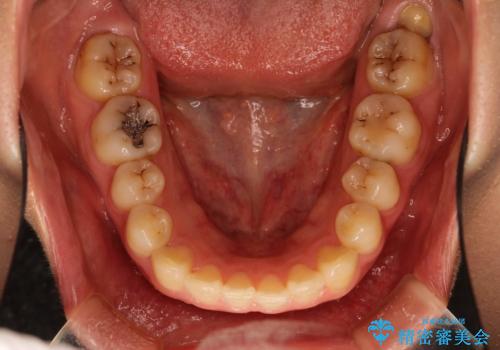

Invisalign インビザライン lite ライト 隙っ歯の改善

- 20代女性

- invisalign lite

- 6ヶ月

- マウスピース矯正による隙間の閉鎖を計画しました。

簡便な処置のため、ライトを選択しました。

かみ合わせが深くない空隙歯列は、最も簡単にその改善が見込まれます。